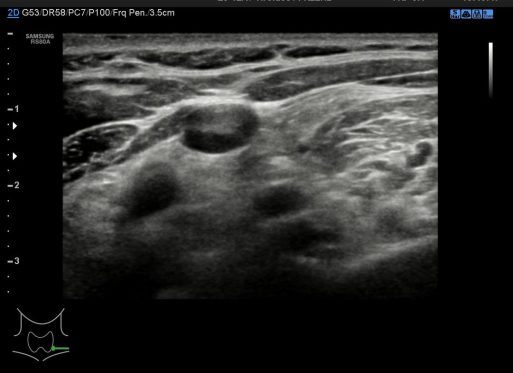

8. Región 1 o Infrauricular (igual que la región 6)

9. Región 2

10. Región 3 o supraclavicular (igual que la región 8)

Cada región del cuello tiene que tener una foto en el estudio y que puedes ver a continuación, el objeto de esta división es la búsqueda de ganglios locorregionales, así como otros hallazgos extratiroideos que pudieran ser de interés, calcificaciones carotídeas, Tiroides ectópico, incluso las glándulas submaxilares (espacio 1 y 6 pegados al 4) y parótidas (espacio 1 y 6, debajo del pabellón auditivo u oreja).

En condiciones normales no tenemos que encontrarnos hallazgos patológicos, pero es habitual ver ganglios que no deben sobrepasar el centímetro de diámetro en eje corto para ser considerados normales, todos los hallazgos no normales deben ser registrados para posterior evaluación del Radiólogo/a.

Each region of the neck has to have a photo in the study and you can see below, the object of this division is the search for locoregional ganglia, as well as other extrathyroidal findings that might be of interest, carotid calcifications, ectopic thyroid, even the submaxillary glands (space 1 and 6 attached to 4) and parotid glands (space 1 and 6, below the auditory pinna or ear).

With this division we guarantee that we review the lateral part of the neck (1,2,3,6,7,8) and the central part – superior to the Thyroid (4) where we find the Tirogloso Conduit. Also the space number 5 or suprasternal notch where ganglia or remains of the Thymus can be hidden. The spaces 1,2,3,6,7,8 follow the length of the Esternocleidomastoideo and all the ganglionic chains of the neck. We must remain very attentive to the situation of the pictogram and how it corresponds to the spaces in the neck of the upper photo. Under normal conditions we do not have to find pathological findings, but it is usual to see nodes that should not exceed one centimeter in diameter on a short axis to be considered normal, all non-normal findings should be recorded for further evaluation by the radiologist.